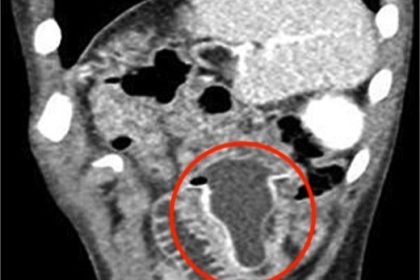

Shock as doctors find baby bottle teat in intestine of boy, 10

Doctors in Saudi Arabia removed a rubber baby bottle teat from a…